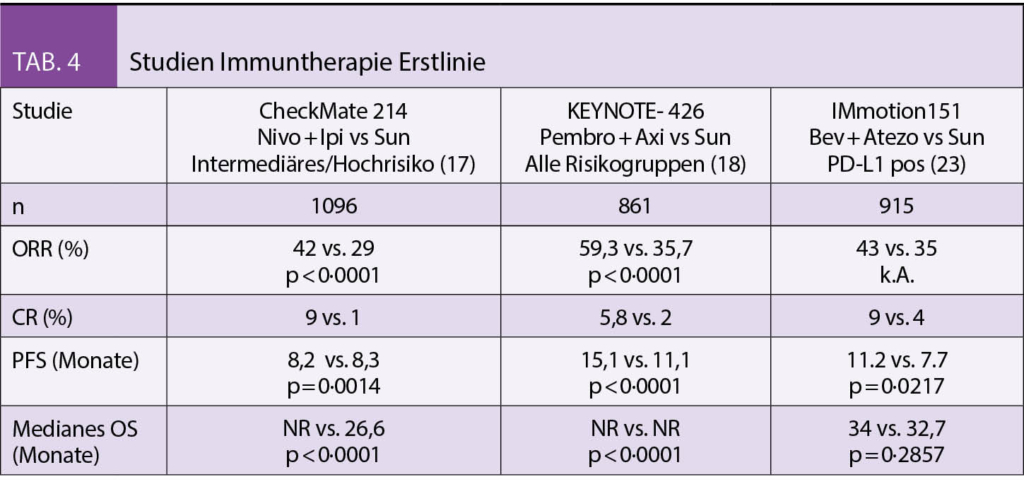

In den letzten Jahren wurden viele neue Substanzen zugelassen. Die TKIs Sunitinib, Pazopanib und Tivozanib zeigten dabei einen signifikanten Vorteil im PFS, jedoch nicht im OS (13-15). Die Substanzen wurden in den Studien mit dem damaligen Standard Interferon-alpha bzw. Placebo verglichen. Eine publizierte Phase-II Studie verglich Cabozantinib mit Sunitinib und konnte für die intermediären und Hochrisikopatienten einen signifikanten PFS Benefit sowie einen Trend zu einem besseren OS zeigen (16). Die alleinige Therapie mit einem TKI in der Erstlinie ist seit den positiven Studienergebnissen mit Immuncheckpointinhibitoren nicht mehr erste Wahl. Prospektive randomisierte Studien mit Nivolumab, einem anti-PD-1 Antikörper in Kombination mit Ipilimumab, einem anti-CTLA-4 Antikörper (CheckMate 214) sowie mit Pembrolizumab, einem Anti-PD-1 Antikörper und dem TKI Axitinib (KEYNOTE-426) – jeweils gegen Sunitinib randomisiert – zeigten in beiden Fällen einen signifikanten Vorteil sowohl im Tumoransprechen, im PFS und auch im OS. Nivolumab/Ipilimumab zeigte diesen im Gegensatz zu Pemprolizumab/Axitinib nur für die intermediären und Hochrisikopatienten (17-18). In der Schweiz können Patienten derzeit in eine klinische Phase II Studie (SAKK 07-17), die eine sequentielle Therapie mit Nivolumab und Ipilimumab in der Erstlinie untersucht, eingeschlossen werden. Mehrere Zentren in der Schweiz nehmen teil (Tab. 4).

Sie kann prinzipiell bei allen histologischen Subtypen auftreten. Klinisch weisen die Patienten häufig ein rasches Tumorwachstum auf und zeigen nur eine geringe und kurz anhaltende Ansprechrate auf herkömmliche TKI-Therapien. Diese Tumoren weisen häufig eine hohe Expression des PD-1 und PD-L1 Liganden auf. In Subgruppenanalysen der Studien mit einer Kombinationsimmuntherapie (Nivolumab/Ipilimumab) oder einer Immuntherapie kombiniert mit einer TKI-Therapie (Pembrolizumab/Axitinib) sowie in der Phase III IMmotion 151 Studie (Kombination des VEGF Inhibitors Bevacizumab mit Atezolizumab, einem Anti-PD-L1 Antikörper) waren die ORR, das PFS und das OS der TKI Gabe der alleinigen TKI Therapie mit Sunitinib überlegen (17) (18) (23). Unabhängig von der Risikogruppe sollten daher alle Patienten mit einer sarkomatoiden Differenzierung eine Immunkombinationstherapie erhalten.